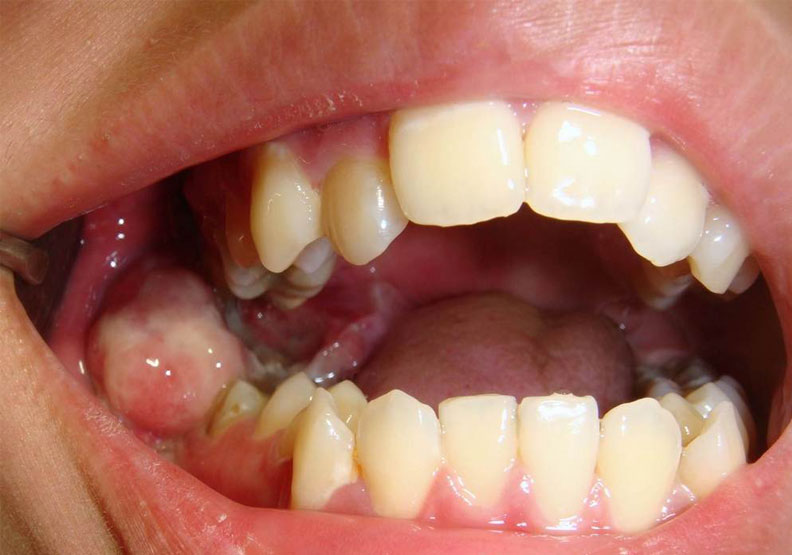

編按:小小智齒竟釀口腔癌!18歲的游同學因右下顎疼痛至牙醫診所就診,經X光檢查發現右下智齒因無法正常生長,有發炎情形。然而,拔除智齒後傷口持續悶痛並伴隨麻刺感,近兩個月之久;期間,持續接受消炎止痛治療仍未改善,最後被轉診至台北慈濟醫院,沒想到經醫師將發炎組織取樣化驗後,診斷出發炎組織已轉變為口腔癌第四期,且癌細胞涵蓋整個右下顎骨。

且即便是沒有長歪的智齒,若無對應咬合的牙齒,也可能因過度萌發影響咬合,或是反覆刮傷周圍的口腔黏膜,長期下來會造成癌變。為了避免這些情形,牙醫師通常會建議盡早將智齒拔除,以絕後患。

值得注意的是,雖然完全深埋在骨頭內的智齒,不會有蛀牙或發炎的風險,可暫時先不拔除,但仍有3%的機率可能轉變為囊腫,或是少部分會轉變成口腔癌,故即使沒有任何不適,也應定期接受影像學檢查。